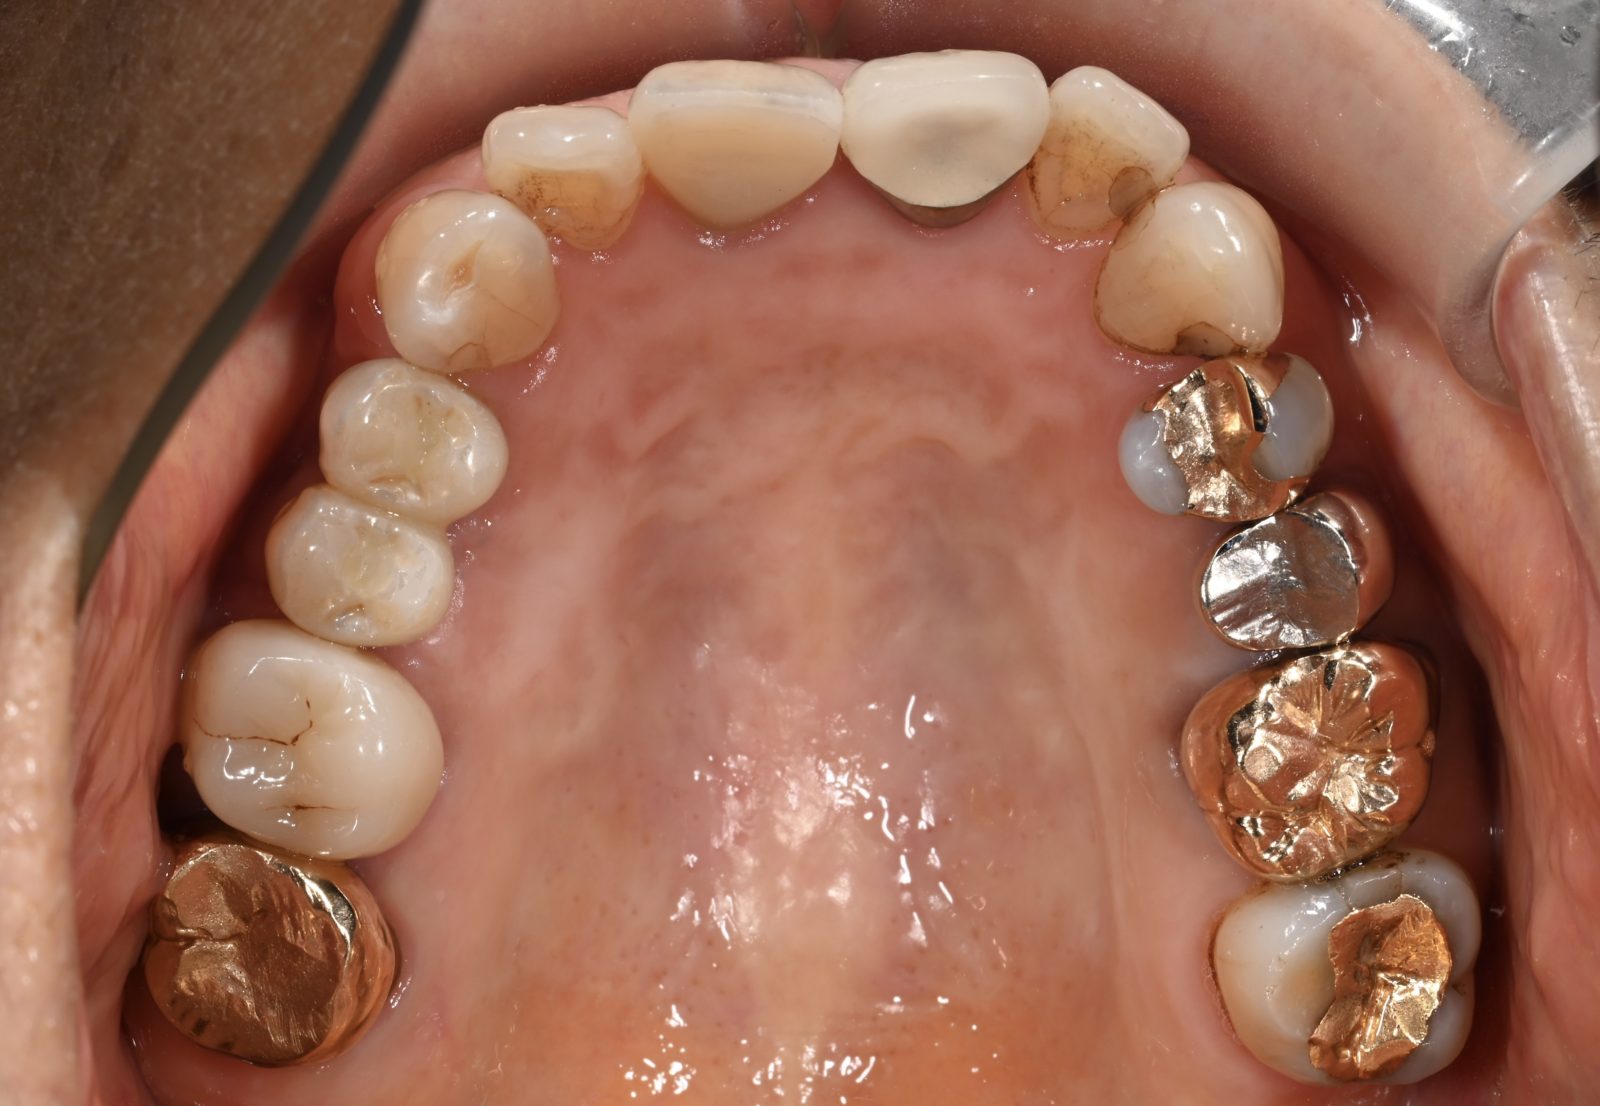

• 治療前

• 治療後